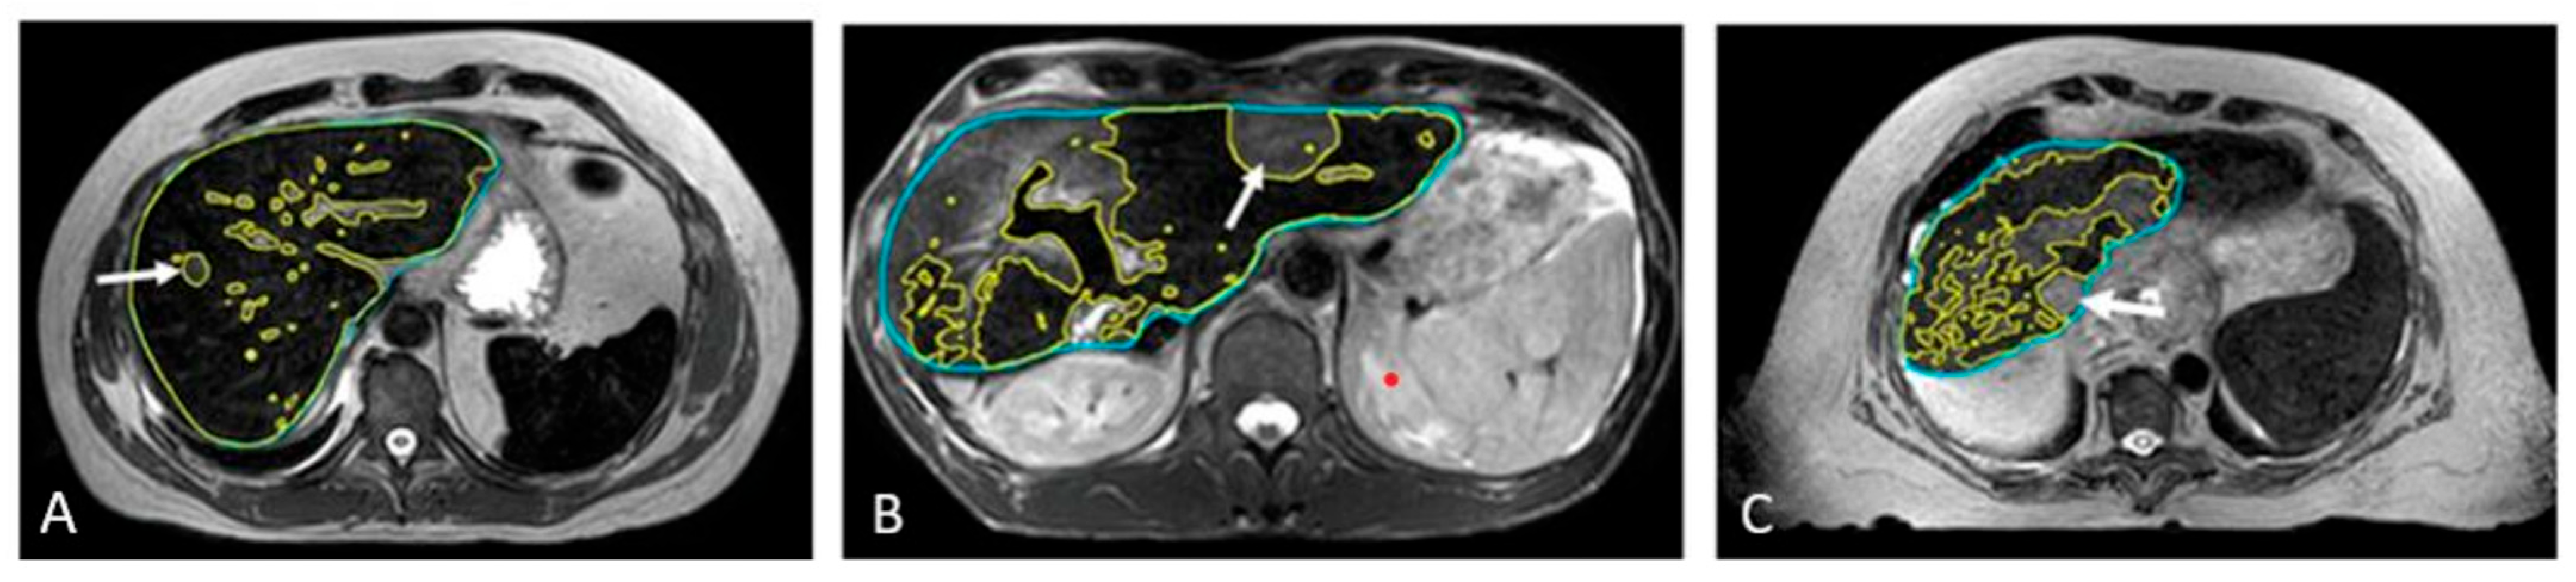

As illustrated in Figure 4, SPIONs ensured consistent tumor visibility throughout the entire treatment course of the MR-guided liver SBRT, which had a median duration of 15 days (ranging from 5 to 28 days).

Figure 4. Example of four daily MR image sets used for online treatment plan adaptation targeting solitary colon cancer metastasis (white arrow) with SBRT (50 Gy in 4 fractions). Days 19, 21, 24, and 28 indicate the time elapsed since Ferumoxytol® injection, corresponding to sequential SBRT fractionation (fx).